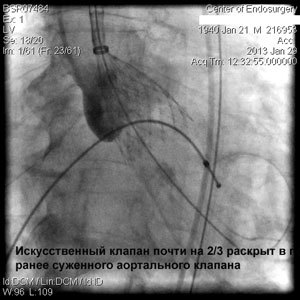

Через прокол (или маленький разрез) в артерии, в сжатом состоянии проводят искусственный клапан, который расширяется при его установке на месте поврежденного аортального клапана. После раскрытия клапан начинает функционировать и восстанавливает полноценную и нормальную работу аорты.